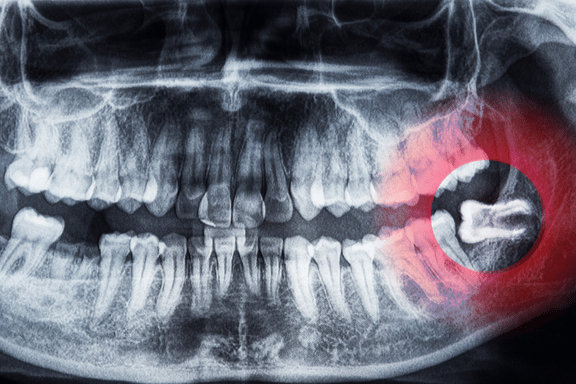

If left untreated, wisdom teeth can become impacted, meaning they don’t emerge fully from the gum line, which can lead to infections, cysts, and damage to neighbouring teeth. This is one of the main reasons early wisdom teeth removal is recommended for long-term oral health and to avoid potential complications later on.

The wisdom teeth removal procedure may sound intimidating, but it’s a relatively routine and efficient process. At Mahogany Oral Surgery in Calgary, we take every step to ensure that you’re comfortable and prepared for the wisdom tooth procedure. Your oral surgeon will assess whether your wisdom teeth are impacted or fully erupted, which will determine the complexity of the surgery.

Once sedated, the oral surgeon will make small incisions in the gums (if necessary) to access the wisdom teeth. If the wisdom teeth are impacted, they may need to be broken into smaller sections for easier removal. After the extraction, the surgical sites are carefully cleaned, and stitches are often used to promote healing.